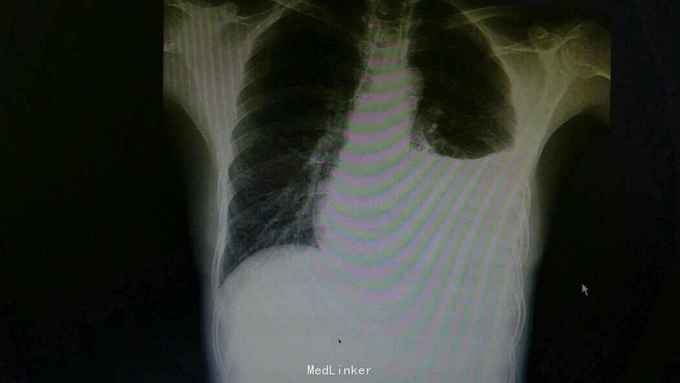

主诉:发热,胸痛10天。 病史:患者10天前无明显诱因出现发热是,伴有乏力,左侧季肋处隐痛,7天前开始出现呼吸困难,平卧时较明显。

查体:左肺呼吸音低,余无特殊。 辅查:胸片提示左侧胸腔积液。

诊断:结核性胸膜炎 治疗:入院予以左侧胸水引流,T-SPORT A68,B24。予以四联抗结核治疗。辅查胸部CT患者左侧胸水减少,病情好转。